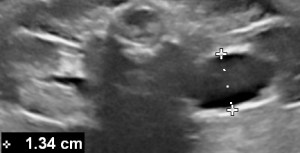

Calyceal distention is best imaged in the sagittal plane.

- Peripheral calyceal distention in the sagittal plane (abnormal).